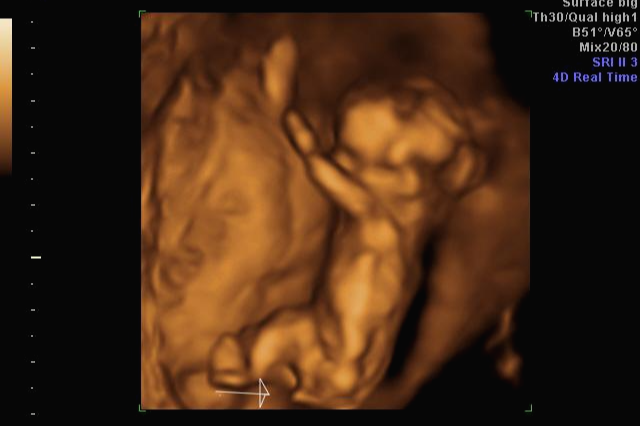

그리고 초음파 봐주시는 분께서 13주차가 되면 정확히 알 수 있으니 다음 주에 오라고 하셔서 일주일 뒤 다시 방문을 했습니다. (위에 사진은 12주 차 때 아들이라고 보여주신 초음파 사진이에요~ 화살표 보면 툭 튀어나와있는 부분을 보여주면서 아들이라고 하셨어요~)

일주만에 더 커있는 우리 트롱이~ 어찌나 꼬물꼬물 귀엽게 움직이던지 ㅎㅎ 트롱이 건강상태를 확인 후 다시 성별을 확인했는데 100프로 아들이라며 지금 병원에서 일을 하시고 경력이 25년 됐다고 믿음을 확실히 주셔서 초음파 검사가 끝나고 바로 부모님께 연락을 드리고 아들 옷 사러 갔어요 ㅋㅋㅋ

아 진짜 전문가는 다르구나~ 이렇게 이른 주수에도 성별을 알 수가 있구나 생각을 했지만 이 시기 때는 성별을 정확히 알 수 없다는 글들을 봐서 살짝~ 의심스럽기도 했지만 그래도 100프로라니깐 ㅎㅎ 믿어보았어요~ 근데 위에 사진을 보면 성별을 알 수 있는 각도 법이 있는데 각도가 딸 같아서 긴가민가~하긴 했지만 의심은 잠시! 전문가 분을 믿기로 ㅋㅋㅋㅋ

입체 초음파 사진은 항상 만족스러워요! 사진 보면 벌써 태어난 아기처럼 어찌 이리 이목구비 뚜렷하고 아이 얼굴이 선명하게 잘 보이는지~ 제아이라 이렇게 사랑스러운 걸까요~? ㅋㅋㅋ